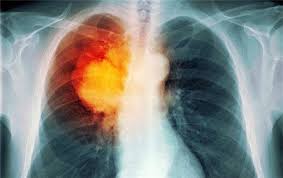

怎么确定是否发生肺癌脑转移

怎样确定是否发生脑转移?简单粗暴的回答是做检查。本着打破破砂锅问到底的精神,再问一句:该做哪些检查呢?大多数人可能会说做个MRI一看不就知道了。这看起来没什么大问题,实际上MRI也是 肺癌脑转移 首选的影像学检查方法,但仍然存在一些不足之处。 ...

肺癌脑转移有什么症状

我们注意到,如何提高肺癌脑转移的生存质量和生存时间已经成为肺腾群友最关心的话题之一。为了答疑解惑,今天我们就好好地聊聊 肺癌脑转移 。       肺癌脑转移 包括什么?首先,我们要清楚一点,脑转移实际上包括脑实质转移和脑膜转移。通常来说, ...